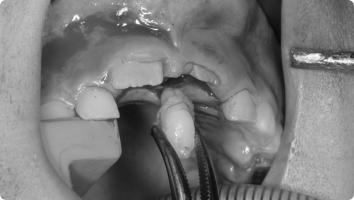

영구치가 나와야 할 시기가 지났는데 잇몸 속에 묻혀 나오지 못하는 치아가 있습니다.

이를 ‘매복치’라고 하며, 흔히 송곳니(견치)에서 많이 발생합니다.

치아가 스스로 나오지 못하면, 교정치료와 함께 개창술을 통해 치아를 밖으로 끌어내야 합니다.

- 국소마취 후, 치아가 묻혀 있는 잇몸을 작게 열어 치아 머리(치관)를 노출시킵니다.

- 치아 표면에 교정용 버튼(장치)을 부착하고, 교정력(작은 고무줄·와이어)을 이용해 치아를 이동시킵니다.

- 수술 자체는 짧고 안전하게 진행되며, 이후에는 교정치료와 병행하여 서서히 치아가 배열됩니다.